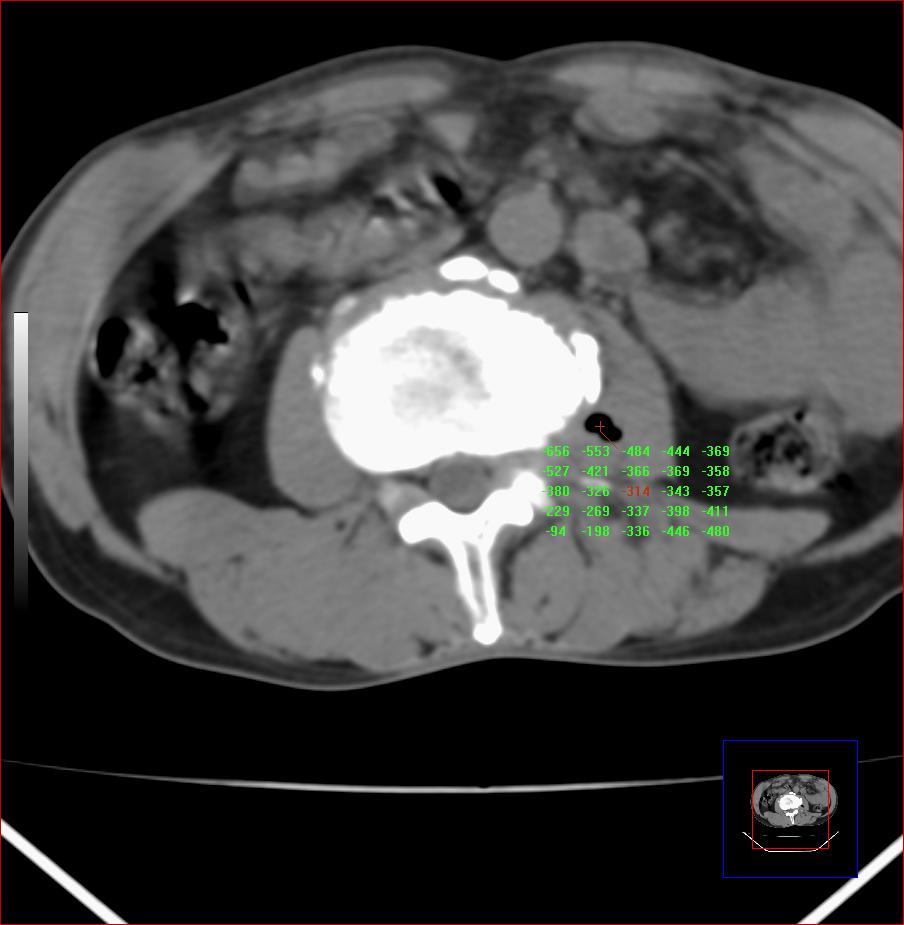

标题: CT24293:左侧腰大肌内气体是什么?

男,40,腰痛来诊,椎间盘膨出。